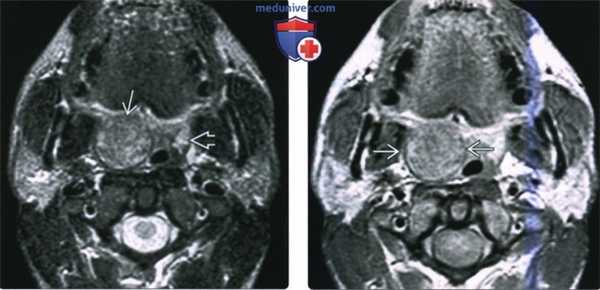

(Слева) МРТ Т2ВИ FS МРТ, аксиальная проекция, на которой визуализируется неходжкинская лимфома правой небной миндалины, контуры образования четкие. Поскольку с возрастом объем лимфоидной ткани снижается, небольшой размер левой небной миндалины является нормой. Плоскоклеточный рак или доброкачественная смешанная опухоль могут выглядеть идентично, и только биопсия позволит установить диагноз лимфомы.

(Справа) МРТ Т1ВИ с КУ, аксиальная проекция, тот же пациент. Лимфома однородно накапливает контрастное вещество. При воспалении миндалины контраст бы накапливался отдельными полосами, в случае интра-тонзиллярного абсцесса в центре образования обнаруживается очаг некроза.